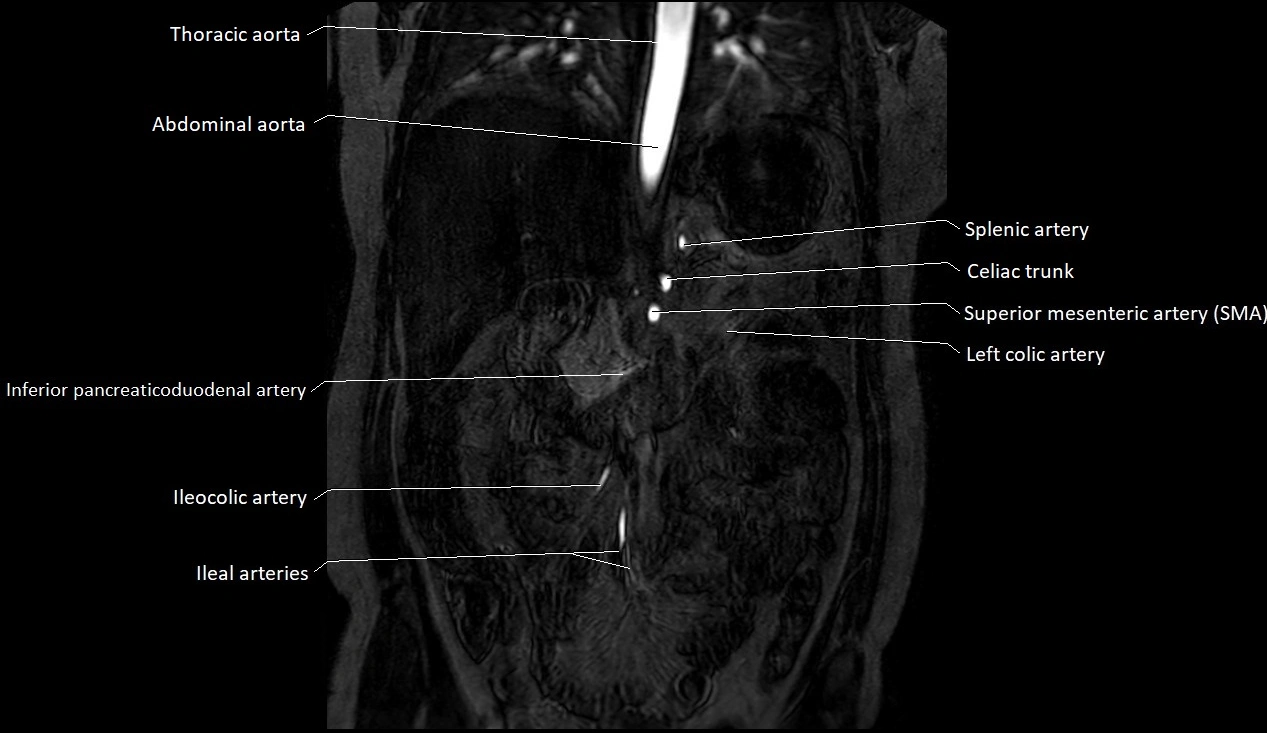

CT images

image